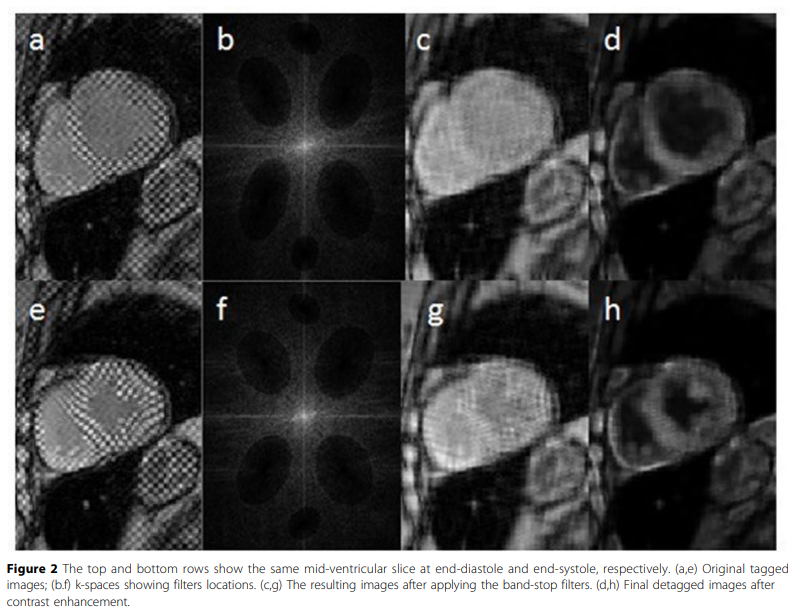

Evaluation of the cardiac global function from tagged magnetic resonance images

Tagged Magnetic Resonance (MR) images are considered the gold standard for evaluating the cardiac regional function. Nevertheless, the low myocardium-to-blood contrast in tagged MR images prevents accurate segmentation of the myocardium, and hence, hinders the quantitative assessment of the global function of the heart. In this work, a method for enhancing the myocardium-to-blood contrast in tagged MR images is proposed. First, the tag pattern in each input tagged MR image is removed using technique based on the image texture and the frequency components of the tag pattern to produce two